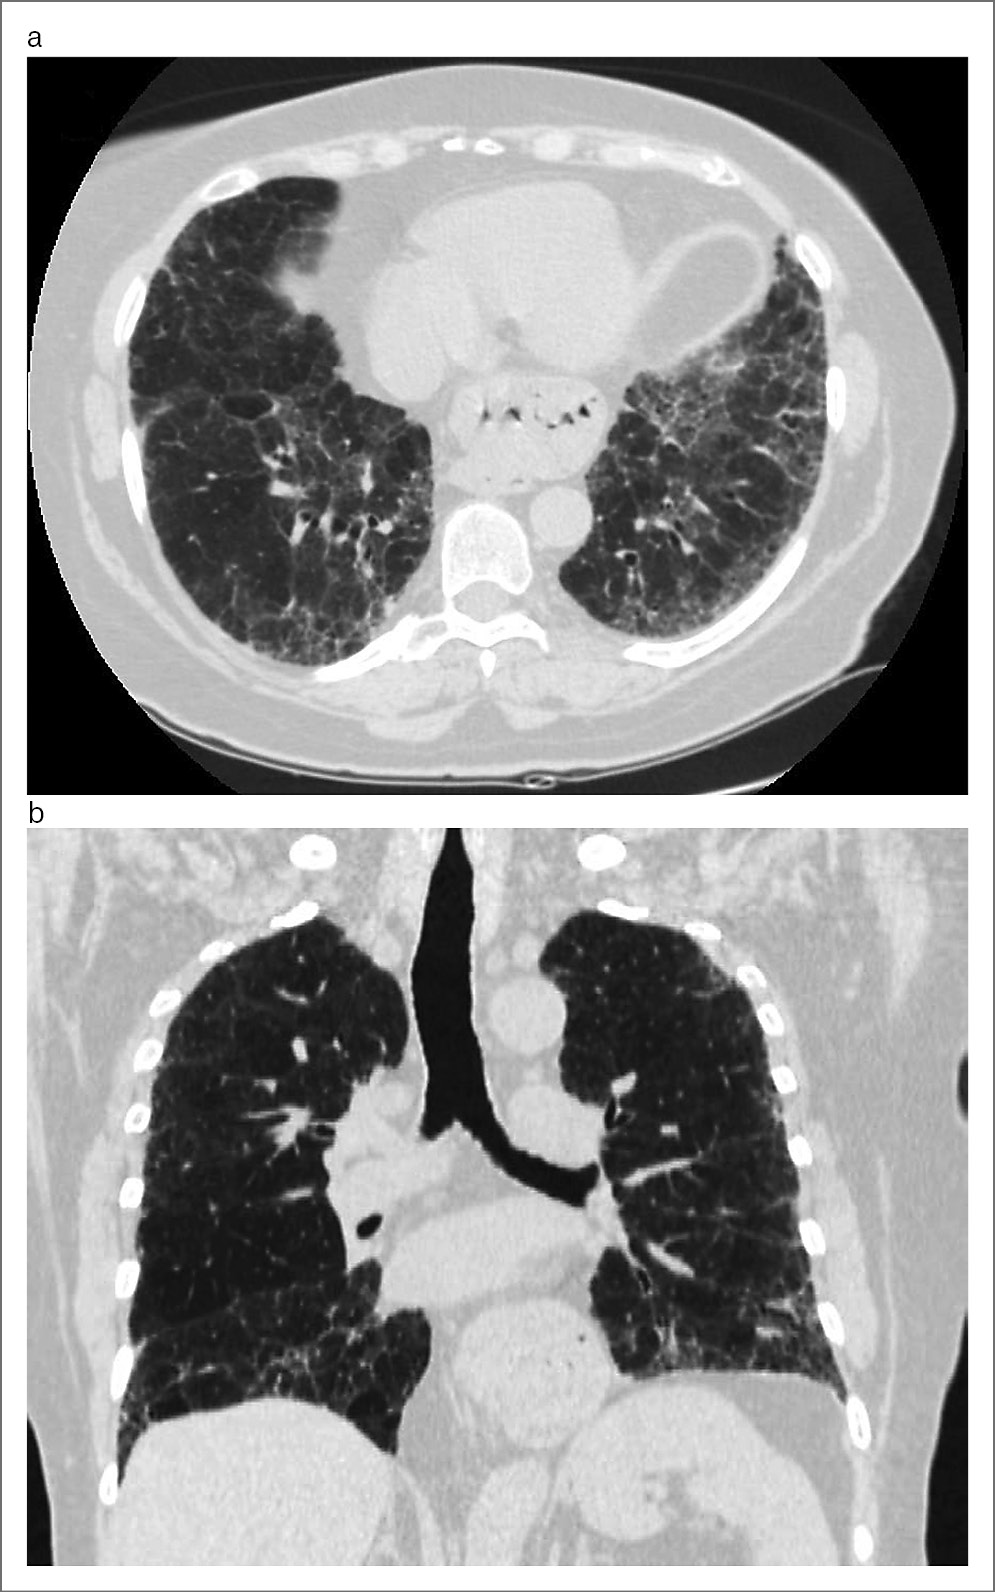

Тракционные бронхоэктазы и бронхиолоэктазы присутствовали у 34 (65,4%) пациентов и представляли собой важный признак фГП. Обычно тракционные бронхоэктазы преобладали в кортикальных отделах легких, несколько реже выявлялись в субплевральных отделах, при этом определялись как в верхних и средних долях, так и в нижних долях с обеих сторон, как продемонстрировано на рис. 3.

Рис. 3. Мужчина, 56 лет, фГП: a – на аксиальном срезе определяются расширенные просветы бронхов, с деформированными стенками (белые стрелки), окруженные зонами ретикулярных изменений, и небольшие участки «матового стекла»; b – реформация во фронтальной проекции с использованием проекций минимальной интенсивности показывает наличие расширенных просветов бронхов в субплевральных отделах на фоне ретикулярных изменений и единичных кист, которые могут соответствовать симптому «сотового легкого».